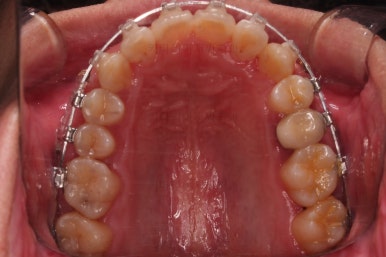

같은 방식으로 지속적으로 반복치료하여 치료를 종료하였어요.

치열이 매우 가지런해졌고 틈새도 없어졌으며 교합도 잘 맞아졌어요.

사이가 다시 벌어지거나 틀어지지 말라고 치아 안쪽면으로 부착형 철사 유지장치를 붙이고 마무리를 했어요.